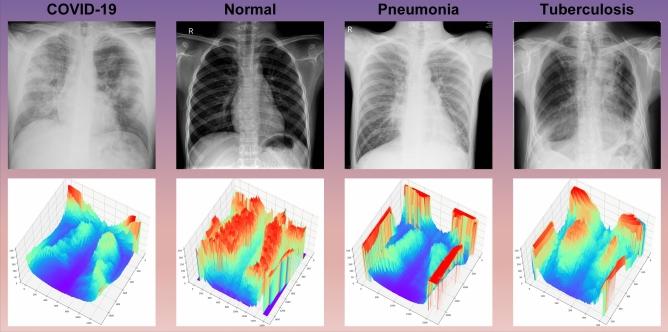

Pulmonary disease can severely impair respiratory function and be life-threatening. Accurately recognizing pulmonary diseases in chest X-ray images is challenging due to overlapping body structures and the complex anatomy of the chest. We propose an adaptive multiscale feature fusion model for recognizing Chest X-ray images of pneumonia, tuberculosis, and COVID-19, which are common pulmonary diseases. We introduce an Adaptive Multiscale Fusion Network (AMFNet) for pulmonary disease classification in chest X-ray images. AMFNet consists of a lightweight Multiscale Fusion Network (MFNet) and ResNet50 as the secondary feature extraction network. MFNet employs Fusion Blocks with self-calibrated convolution (SCConv) and Attention Feature Fusion (AFF) to capture multiscale semantic features, and integrates a custom activation function, MFReLU, which is employed to reduce the model's memory access time. A fusion module adaptively combines features from both networks. Experimental results show that AMFNet achieves 97.48% accuracy and an F1 score of 0.9781 on public datasets, outperforming models like ResNet50, DenseNet121, ConvNeXt-Tiny, and Vision Transformer while using fewer parameters.

肺部疾病会严重损害呼吸功能并危及生命。由于身体结构重叠和胸部解剖结构复杂,在胸部X光图像中准确识别肺部疾病具有挑战性。我们提出了一种自适应多尺度特征融合模型,用于识别肺炎、肺结核和新冠肺炎等常见肺部疾病的胸部X光图像。我们引入了一种自适应多尺度融合网络(AMFNet)用于胸部X光图像中的肺部疾病分类。AMFNet由一个轻量级的多尺度融合网络(MFNet)和作为二级特征提取网络的ResNet50组成。MFNet采用带有自校准卷积(SCConv)和注意力特征融合(AFF)的融合块来捕获多尺度语义特征,并集成了一个自定义激活函数MFReLU,用于减少模型的内存访问时间。一个融合模块自适应地组合来自两个网络的特征。实验结果表明,AMFNet在公共数据集上达到了97.48%的准确率和0.9781的F1分数,在使用更少参数的情况下优于ResNet50、DenseNet121、ConvNeXt-Tiny和视觉Transformer等模型。